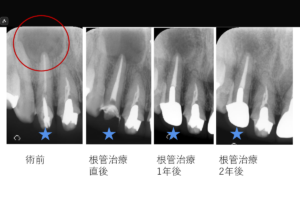

抜髄は、虫歯などで炎症を起こした神経を取り除く最初の処置です。一方、再根管治療は、過去に治療した根管に細菌が再感染し、根の先に膿が溜まった際に行うやり直しの治療です。どちらも再発を防ぐには、マイクロスコープを用いた精密な清掃と、ラバーダム等による徹底した無菌的処置が成功の鍵となります。

根管治療後の再発や原因不明の症状には、必ず病態的な理由が存在します。未処置根管、側枝感染、器具破折、不完全な感染除去など、専門的診断によって初めて特定できる問題も少なくありません。当院には、他院で改善しなかった症例が多数来院されます。東京は品川駅目の前で歯内療法(根管治療)専門に自由診療で高度な治療を提供している「渡辺歯内デンタルオフィス品川」では、歯内療法専門医の立場から、症状の背景を正確に解析し、再治療の可否と限界を含めて適切に判断します。